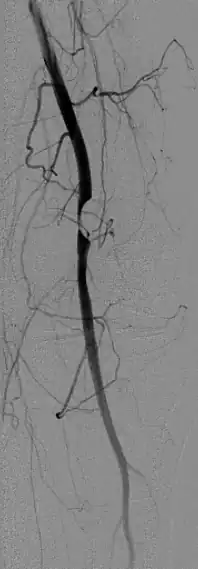

Klinisch stellt sich das Krankheitsbild mit einer wechselnden Beschwerdesymptomatik dar, die eine Abhängigkeit von der Belastung des betroffenen Kniegelenks zeigt.[13] Die Durchblutungsstörungen können dabei unter Umständen im Sinne eines Provokationstestes durch Beugung im Kniegelenk ausgelöst oder verstärkt werden.[4][14] Als bildgebende Diagnostik wird neben dem Ultraschall mit Duplexsonographie die Computertomographie und spezifischer und ohne Strahlenbelastung die Magnetresonanztomographie eingesetzt.[4] Diese zeigt oft gekammerte, runde bis länglich ovale Zysten in der Gefäßwand. Eventuell vorhandene zusätzliche Ganglien am Kniegelenk können in der gleichen Untersuchung erfasst werden. Die Zysten sind signalintens in T2-gewichteten, signalarm in T1-gewichteten Bildern und nehmen kein Kontrastmittel auf. Die Angiographie zeigt bei ansonsten in der Regel unauffälligen Gefäßen eine umschriebene, scharf begrenzte, bogige Kontrastmittelaussparung, die je nach Ausdehnung der Zysten auch mehrfach und von beiden Seiten vorkommen kann. Man spricht vom Scimitar-Zeichen (Scimitar = Krummsäbel).[8] Dieser ursprünglich in der konventionellen Angiographie verwendete Begriff wird heute auch in der Magnetresonanztomographie, insbesondere in der MRA gebraucht.